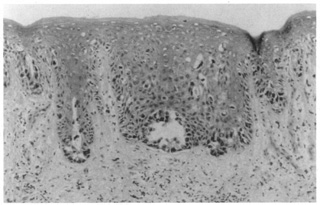

The ichthyoses are a group of inherited disorders of keratinization characterized by dryness and excessive scaling of the skin. Ichthyosis vulgaris (autosomal dominant) often demonstrates fine scaling of the lids, lashes, and surrounding skin; X-linked ichthyosis, additionally, may show large, darker, polygonal scales. One of the two rare autosomal recessive types, lamellar ichthyosis, demonstrates large, thick scales often with ectropion of the lids and conjunctival changes. In ichthyosis vulgaris, there is compact orthokeratosis overlying a markedly diminished or absent granular layer without significant inflammation in the dermis (Fig. 16). X-linked and autosomal recessive ichthyoses also show compact orthokeratosis, but the changes in the granular layer are not distinctive. In autosomal dominantly inherited epidermolytic hyperkeratosis, a distinct histologic change is characterized by intracellular edema, vacuolization of keratinocytes, and the appearance of large, clumped keratohyalin granules, especially in the superficial portions of the epidermis.

Fig. 16. A. Ichthyosis vulgaris showing compact orthokeratosis with a markedly diminished granular layer. B. Epidermolysis bullosa, recessive dystrophic type, with a noninflammatory subepidermal bulla.